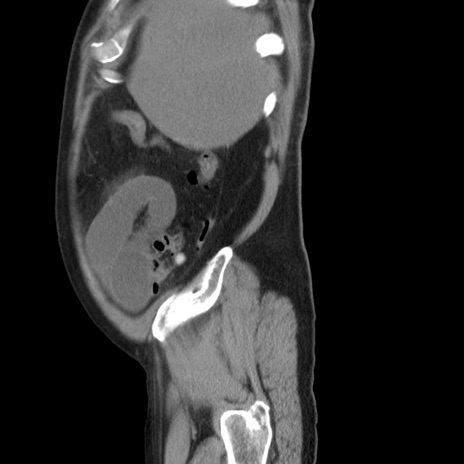

症例20(矢状断像)

【症例】 60歳代男性

【主訴】 腹部膨満、嘔吐

【現病歴】5日前頃より倦怠感を認め食事量減少し4日前の朝嘔吐、食事摂取困難となった。 3日前近医受診し点滴施行され整腸剤などを処方された。 当日他院を受診し、腹部膨満著明、炎症反応の上昇(CRP10.8、WBC11200)あり、紹介受診となる。

【身体所見】 意識JCS1 受け答えがはっきりしないBP 111/57mHg、 P 67bpm、、BT35.2°C、SpO2 97%(RA)、 腹部:膨隆、打診で鼓音あり、全体的に圧痛有り、腸蠕動音(-)、反跳痛ははっきりせず。

【データ】WBC 11400、CRP 14.20